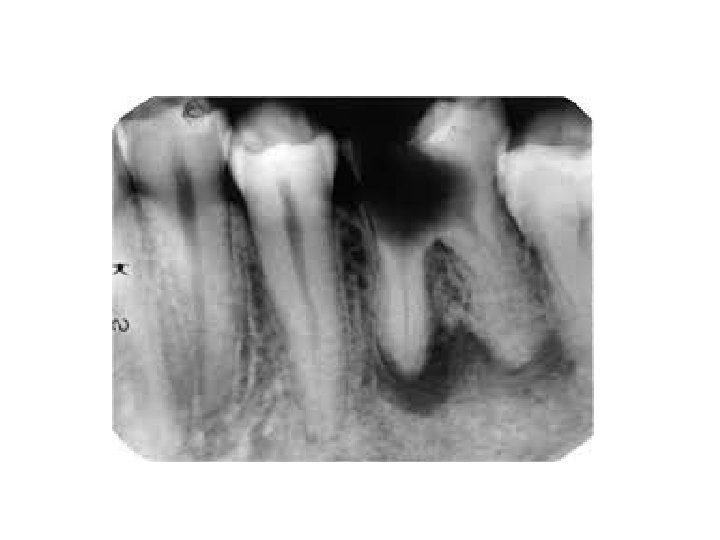

Abcessus periapicalis chronicus • abgekapselte Ansammlung von Eiter • Symptome: spontaner Zahnschmerz, Perkussionsschmerz Fistula, Gaumenschwellung Eiterbeule an der Gaumen • Röntgen: Irregulare und unscharfe Grenze, Aufhellung, (Granuloma ist dunkler)